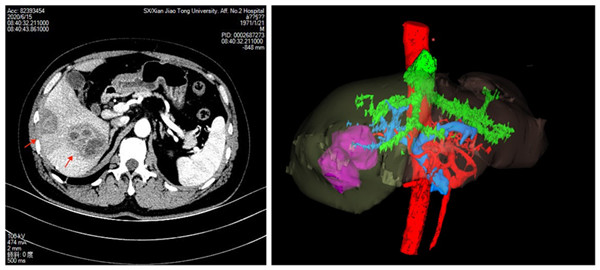

病人CT 病人肿瘤3D重建

某男性患者,49岁,因意外发现肝脏占位病变,辗转多家医院后慕名找到我院普通外科曹罡主任医师,患者在积极完善各种术前检查后,发现肝内占位病变均位于肝脏右叶,经穿刺活检后不能排除恶性可能,经曹罡主任医师、刘阳副主任医师认真评估患者身体及肿瘤状态后与患者充分沟通,决定采用微创技术切除肝脏巨大肿瘤。经术前周密准备和手术规划后,由曹罡主任医师亲自主刀,刘阳副主任医师、王加中医师、陈硕医师作为助手,由麻醉科吕建瑞主任率领,赵亚琴教授、熊虹飞团队保驾护航,在精准中心静脉压的控制下,与手术室赵丽燕率领的张慧、李豪护士的全力配合,成功实施了腹腔镜下解剖性肝段切除术,手术顺利,术中出血量仅为200ml。